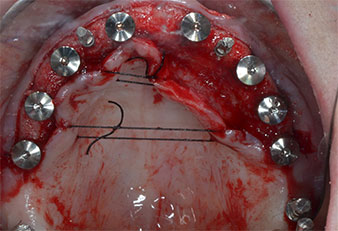

Para marcar las posiciones del implante y realizar la preparación piloto, se utilizó un inserto piezoeléctrico (Piezomed I1) con revestimiento de diamante y forma de llama (figura 3). Se tomaron precauciones para realizar movimientos hacia arriba y hacia abajo, con una potencia reducida, una irrigación completa y una baja presión (por debajo de 300 g). A continuación, se aplicó un inserto piloto (Piezomed I2A/I2P) para aumentar el diámetro inicial de 2 mm de los sitios de implante (figura 4), seguido de un inserto de 3 mm (Fig. 5).

En el caso que nos ocupa, no se utilizaron los insertos Z25P ni Z35P debido a la existencia de un hueso posterior relativamente blando, que se trató sin problemas con el I3A/I3P.

Debido al hueso relativamente duro (D2) existente en el sector anterior, los sitios de los implantes largos de 10 mm de las posiciones 11 y 21 se finalizaron con una fresa rotatoria de 4 mm de diámetro, en combinación con un contra-ángulo quirúrgico WS-75 L de W&H, el motor de implantes Implantmed de W&H y el módulo opcional Osstell ISQ de W&H. En cambio, debido a la existencia de hueso blando, los sitios posteriores se prepararon hasta un diámetro final de 3 mm utilizando el inserto Piezomed I3P. Por último, los implantes se colocaron a nivel crestal para su osteointegración durante tres meses (figuras 6-10). La prótesis existente se mantuvo sobre cuatro implantes provisionales (figura 8).